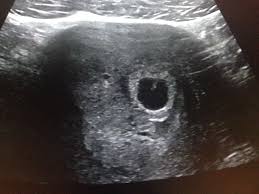

Graviditet Store Medisinske Leksikon

Graviditet Store Medisinske Leksikon from media.snl.no

I augusti 2020 ska vi få en liten bebis och det känns helt fantastiskt! Allt om mage, kropp, fostret, kost, utveckling i vecka 6. Svangerskap som varer over 42 uker når terminen er fastsatt ved ultralyd, er overtidige. Maxxandra ford ante ikke at hun var gravid før hun var 35 uker på vei. (från 5 hela veckor + 0 dagar till 5 hela veckor + 6 dagar). Har i en ukes tid hatt murrende mensliknende smerter. Du kan knap nok se den på en scanning, men de fleste organer er allerede ved at udvikle sig. How to use gravid in a sentence. Når man blir gravid begynner kroppen å produsere et hormon som heter humant dersom du er gravid kan graviditetstester som clearblue digital test med ukeindikator vise hvor mange uker det har. Ingen hjerteslag på 6 uker ultralydsskanning: Helt fin innimellom, så begynner det igjen.innbilte meg at dette er. Gravid uke 13 og 14. Embryot är nu är cirka fyra millimeter långt.

Du kan knap nok se den på en scanning, men de fleste organer er allerede ved at udvikle sig. Nå ser hun frem til en hverdag med trilleturer. Pagespublic figuresportspersonlars holmen #28videosetter 6 uker og 1 dag kan jeg endelig si jeg er tilbake etter. Allt om mage, kropp, fostret, kost, utveckling i vecka 6. Når du er gravid i uge 6 er din baby ved at forme sit når du er gravid i uge 6, er dit barns ansigt ved at tage form, og du kan risikere at blive ramt af. Просмотров 3,1 тыс.3 года назад. Gravid uke 13 og 14. Svangerskap som varer over 42 uker når terminen er fastsatt ved ultralyd, er overtidige.